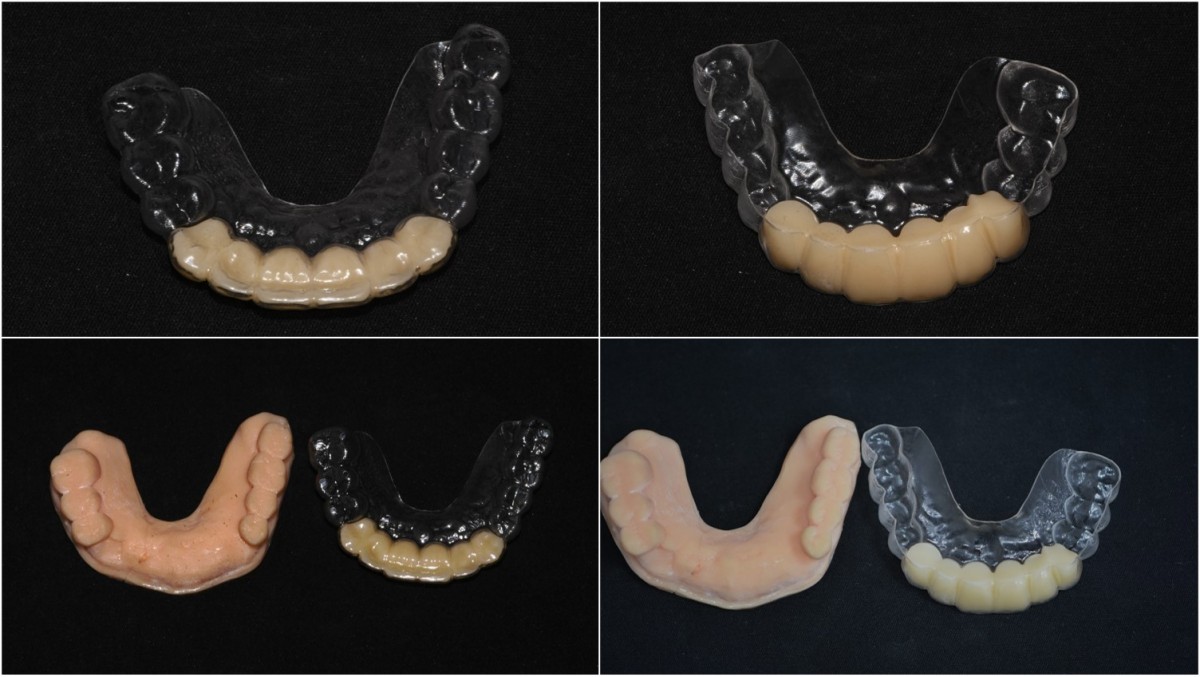

▲Fixture to be placed. Arum® implant NB1